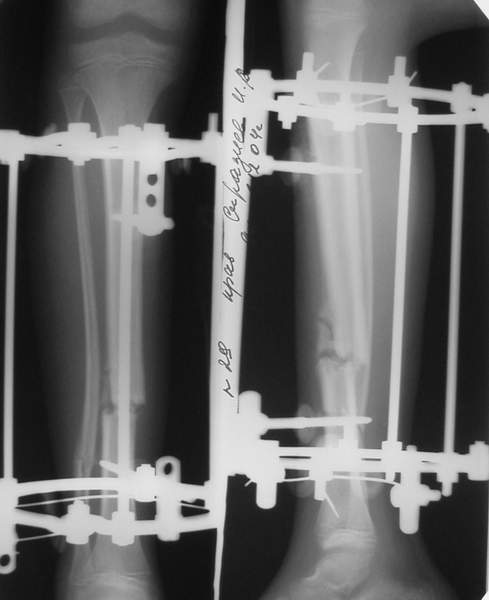

МТ мы используем, конечно, не только на голени. В прилагаемом примере у парня при поступлении была наружная ротация 40 гр. и "полумертвый" коленный сустав. Можно был бы, конечно, до конца использовать полную компоновку. Но для того он и есть метод выбора.